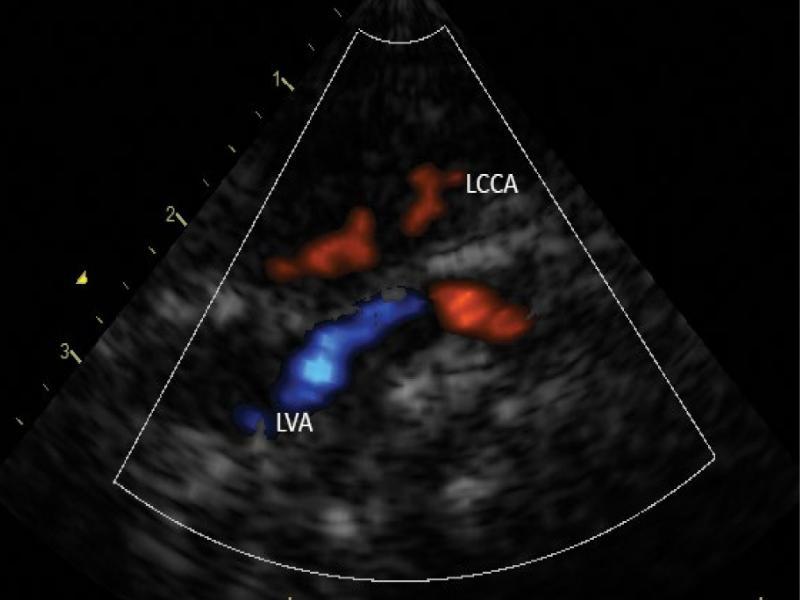

We attempted to experimentally clamp the posterior descending artery (PDA) during echocardiography-guided cardiac correction and found no deficit in blood supply in the left upper limb. PDA was ligated and divided. A total correction of tetralogy of Fallot was performed. The post-operative period was uneventful. Postoperative ultrasonography still showed reversed flow in the left vertebral artery (LVA), representing the only supply of the left subclavian artery (LSA) (Fig. 10 and Fig. 11 show altered flow in the left common carotid artery and left vertebral artery after defect correction and ductus arteriosus closure). The flow in both arteries was systolic and high-resistance, which confirmed the decreased volume of cerebral steal. It may be therefore concluded that the closure of ductus arteriosus reduced the risk of cerebral perfusion deficit, with maintained blood supply to the left upper extremity.

Postoperative assessment. Visible carotid segments of LCCA and LVA. Systole. The direction of the flow in the left vertebral artery is opposite to the flow in the left common carotid artery